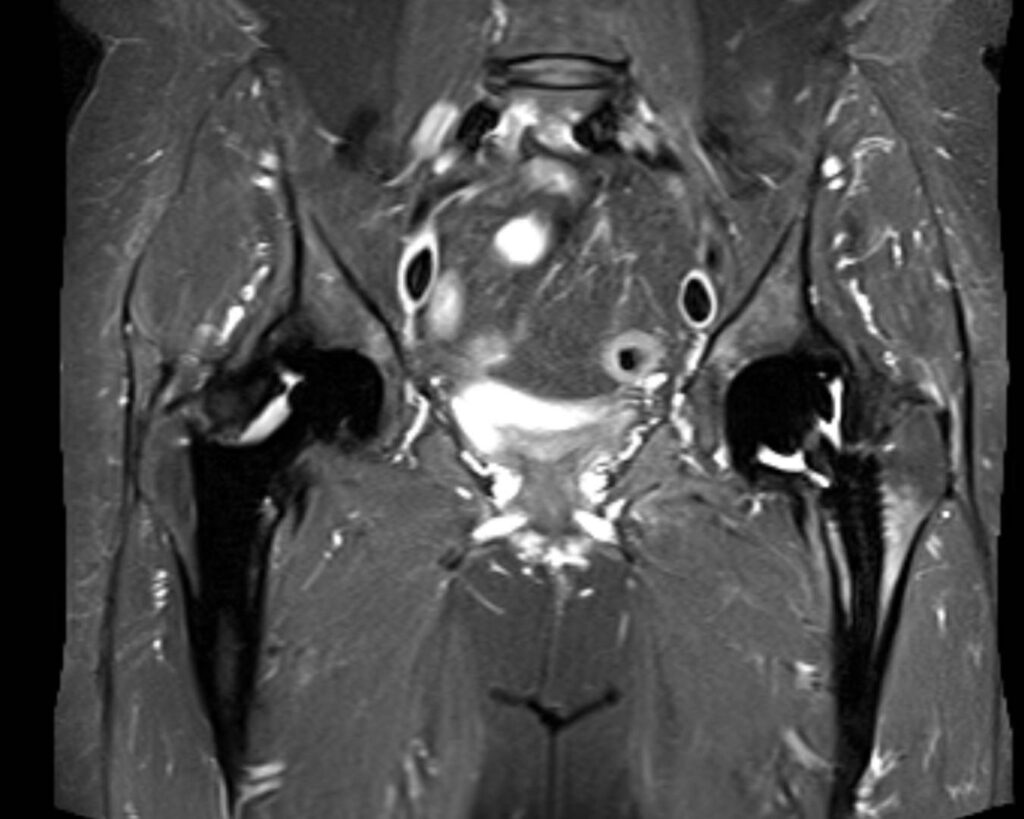

Die Magnetresonanztomographie des Beckens, kurz MRT Becken genannt, ermöglicht es den Bereich des Beckens bildlich darzustellen. Hierbei ist nicht nur der knöcherne Teil des Beckens zu sehen, sondern auch Gelenke und insbesondere Organe, die sich im Beckenbereich befinden. Die MRT Becken ermöglicht strahlenfreie und präzise Bildgebung.

Das Becken ist die zentrale Verbindung zwischen unseren Beinen und dem Rest des Bewegungsapparats. An die Beine schließt das Hüftgelenk an und an die Wirbelsäule das sogenannte Iliosakralgelenk. Das Becken ist von zahlreichen Muskeln und Bändern umgeben, die für das Gehen und Stehen unerlässlich sind. Im Beckenbereich, insbesondere auf einer Magnet-, oder Kernspintomographie zu sehen, befinden sich die Nieren, Harnblase, ein Teil des Darms, unsere Geschlechtsorgane und Weichteilstrukturen, sowie Blutgefäße. Bei Beschwerden im Beckenbereich kann eine Magnetresonanztomographie (MRT) des Beckens diagnostisch hilfreich sein.

Die Magnetresonanztomographie überzeugt durch ihren hohen Weichteilkontrast. Damit eignet sich dieses bildgebende Verfahren ideal zur Beurteilung von Tumoren, Entzündungen und Nekrosen von Knochen, Weichteilen und Organen sowie von Schäden am Kapselbandsystem der Gelenke und inneren Gelenkverletzungen.

Der Körper wird zweidimensional Schicht für Schicht gescannt, wodurch zahlreiche Querschnittsbilder entstehen. Diese werden dann am Computer übereinander geschichtet, sodass ein dreidimensionaler Eindruck entsteht. Auch rechnerisch ist eine exakte 3D-Rekonstruktion möglich, sodass die in der MRT entstandenen Bilder anschließend aus jedem Blickwinkel betrachtet werden können. Anhand dieser MRT Bilder können verschiedenste Strukturen und Funktionen des Beckens und Körperinneren detailliert beurteilt werden.

Eine MRT des Beckens kann anatomische Strukturen und insbesondere Gewebe darstellen.

• Beckenknochen: Der Knochen des Beckens wird einschließlich des Beckenrings, Kreuzbeins und der Hüftgelenke detailliert dargestellt. Insbesondere bei Arthrose in der Hüfte ist dies hilfreich.

• Weichteilstrukturen: Im Beckenbereich befinden sich Muskeln, Sehnen, Bänder und Faszien. Sollte es hier zu Verletzungen oder Erkrankungen der jeweiligen Struktur gekommen sein, kann dies in einem MRT Bild sichtbar sein.

• Harntrakt: In der MRT sind Nieren, Harnleiter und Harnblase zu sehen. Diese gehören zu den Organen der Harnwege.

• Geschlechtsorgane: Die Darstellung der geschlechtsspezifischen Organe ist ebenfalls durch eine MRT des Beckens möglich. Hierbei sind Gebärmutter, Eierstöcke, sowie Eileiter oder die Prostata sichtbar. Die MRT Becken unterstützt die Früherkennung von Anomalien, die Diagnostik und kann der Verlaufskontrolle dienen.

• Lymphknoten: In unserem Leistenbereich, der im Beckenbereich liegt, befinden sich Lymphknoten. Die MRT des Beckens kann bei der Beurteilung von lymphatischen Erkrankungen, sowie Metastasen hilfreich sein.